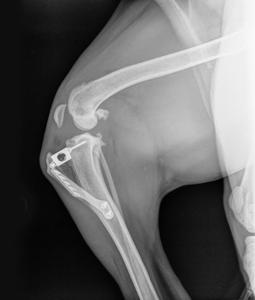

- 방사선(X-ray) 촬영

| 수술적 치료 | 완전 파열, 대형견, 활동량이 많은 경우, 보존적 치료에 효과 없을 때 필요. 대표적 수술로 TPLO, TTA, 인공 인대 대체 등이 있음 |